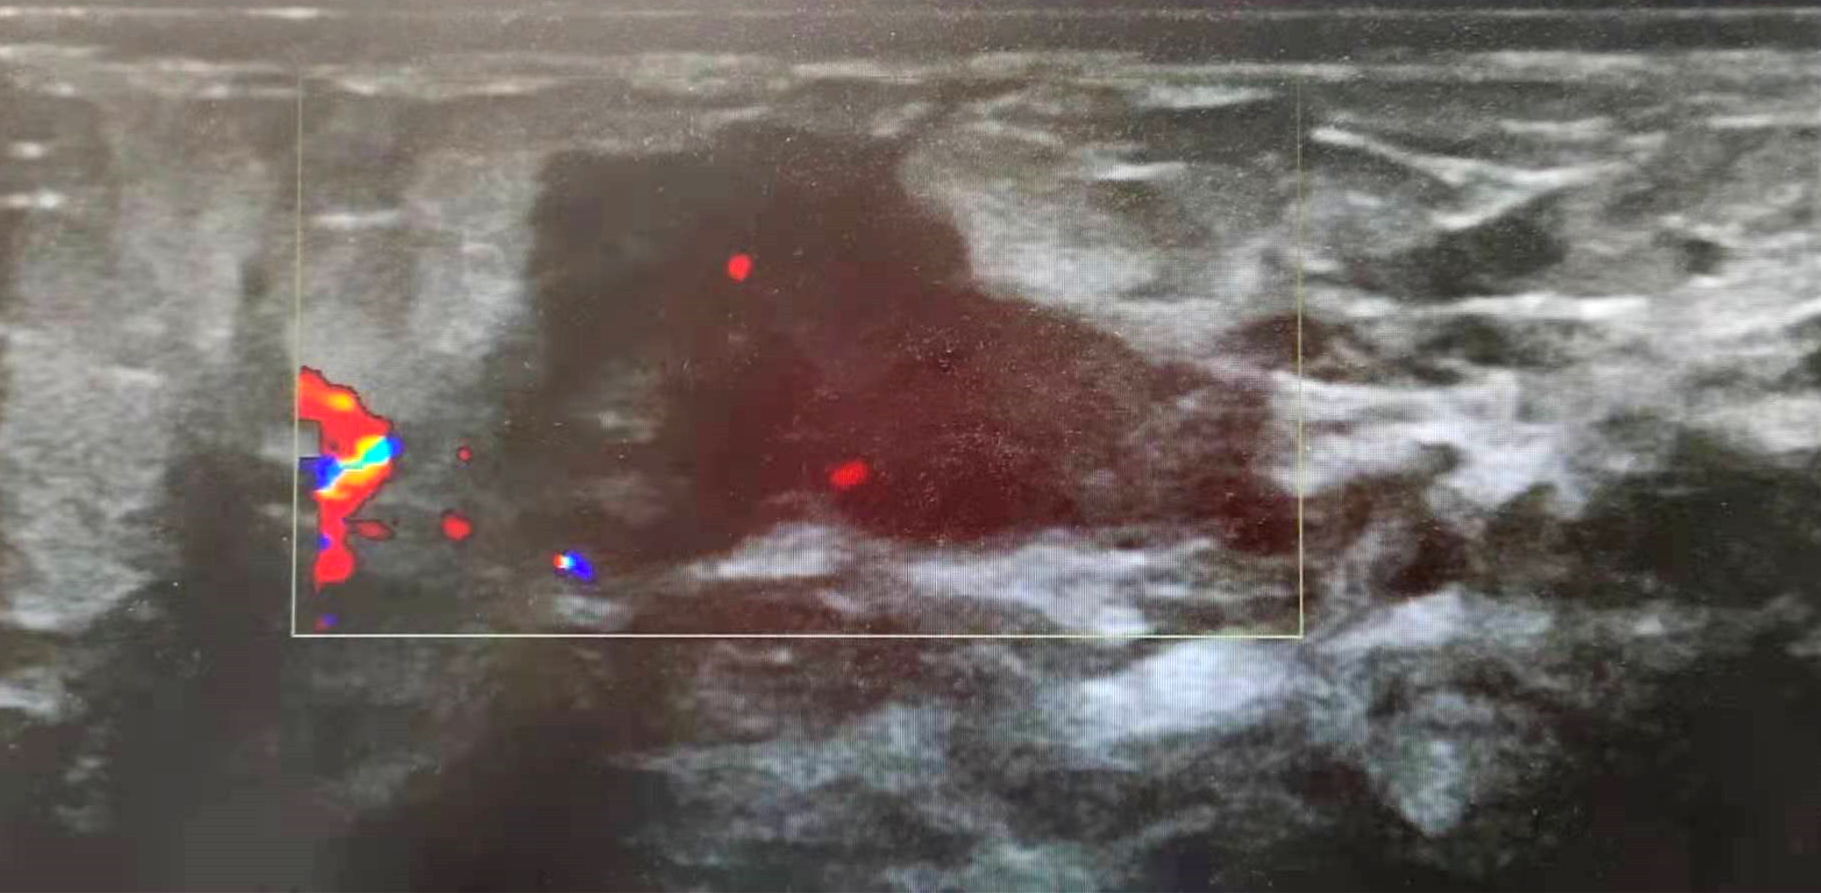

近日,我院妇科门诊主治医师罗桂兰在为患者查体时,发现乳房处凸起的包块,不像是单纯的乳汁淤积所致,遂找到超声室科主任郑岩岩主治医师行地毯式超声扫查,诊断为右乳包块(BI-RADS 4级)腋窝淋巴结肿大,遂收住院,进行了手术治疗,手术顺利,现在康复中。

症状及超声表现:妊娠期或者妊娠相关乳腺癌是指在妊娠期间、产后一年或哺乳期任何时间诊断的乳腺癌。30岁以下的女性中,高达20%的乳腺癌和怀孕有关。发病率是15-35/100000例。发病率不高,但大多数分化差并且确诊时已经是晚期。乳汁淤积形成的硬块,多半是突然出现,有明显的疼痛,甚至由皮肤红肿,而乳腺癌的硬块一定是逐渐由小变大的过程,初发现时一般很少有疼痛或者红肿。若早期发现,超声可表现为增厚且回声增强不均的腺体层内见不均质低回声,形态不规则,边界不清楚,纵横比大于1,内部可伴细小钙点。随病情进展,低回声结节可迅速扩散,表现为片状不均质低回声区,无明显边界,形态不规则,内减沙粒样微钙化灶,血供丰富,RI高。伴同侧腋窝及锁骨上淋巴结转移时,表现为腋窝的低回声结节,单发或多发,大小不等,淋巴门结构不清或偏心性。